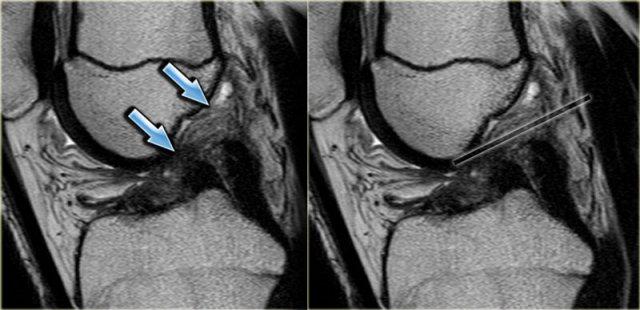

Hãy quan sát hình ảnh bên trái và cố gắng xác định vấn đề của sụn chêm này là gì.

Như bạn đã đoán được qua tiêu đề của đoạn này, đây là một trường hợp sụn chêm lật (flipped meniscus).

Sụn chêm lật là một dạng đặc biệt của rách dạng quai xô (bucket-handle tear).

Sụn chêm lật xảy ra khi mảnh vỡ của sừng sau bị lật ra phía trước, khiến sừng trước của sụn chêm có vẻ to hơn bình thường.

- Thân sụn chêm ngoài.

- Sừng sau quá nhỏ và sừng trước có vẻ to hơn với đường viền không đều.

- Thoạt nhìn có vẻ như có một đường rách dọc ở sừng trước, nhưng thực chất phần sau của cấu trúc này chính là phần lật của sừng sau bị rách.

Cấu trúc phía trước là sừng trước.

Cũng cần lưu ý tình trạng phù tủy xương khu trú và dấu ấn lõm sụn khớp. - Cấu trúc phía trước là sừng trước.

- Một số bất thường ở phần sau.

- Phần sau di chuyển về phía đuôi (caudal).

- Trong hố gian lồi cầu là điểm nối giữa mảnh di lệch và phần còn lại của sừng sau.